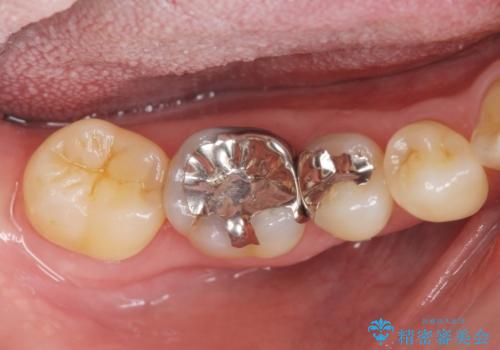

インレーとクラウン 銀歯をセラミックにやりかえ